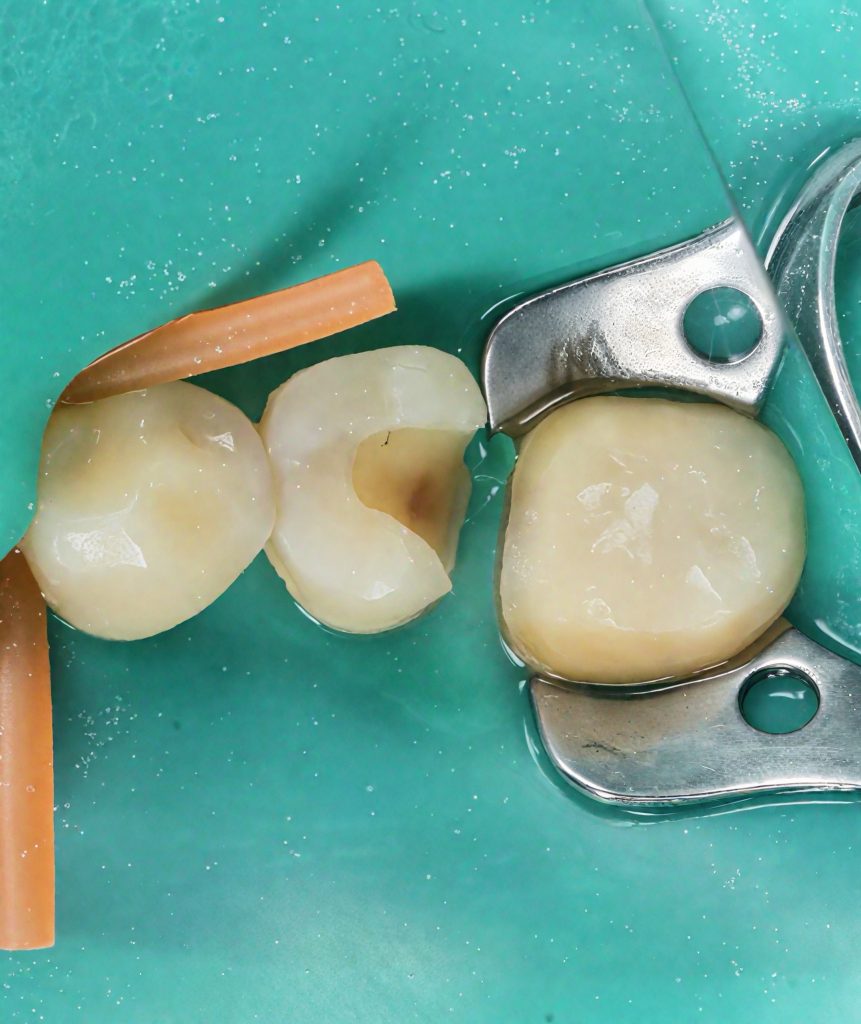

2️⃣ Isolation & Preparation

Rubber dam applied for moisture control. Caries removed conservatively, preserving pericervical dentin. (Fig 2)

- Fig 2: Rubber-dam isolation and conservative preparation.